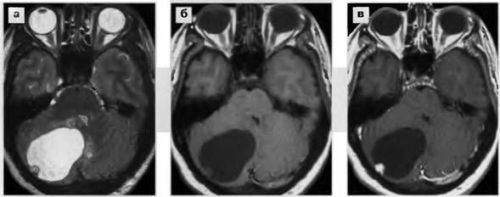

Запрещено взятие люмбальной пункции при объемных образованиях задней черепной ямки или височной доли головного мозга. В таких ситуациях забор даже небольшого количества ликвора может вызвать дислокацию мозговых структур и стать причиной ущемления ствола мозга в большом затылочном отверстии, что влечет за собой немедленный летальный исход.

При опухолях головного мозга проводить люмбальную пункцию можно только по жизненным показаниям, так как высок риск развития дислокации мозговых структур

Возникают при резком падении ликворного давления. Такое возможно при наличии объемных образований задней черепной ямки. Чтобы избежать такого риска, перед тем, как взять пункцию, необходимо выполнить исследование на признаки дислокации срединных структур головного мозга (ЭЭГ, РЕГ).